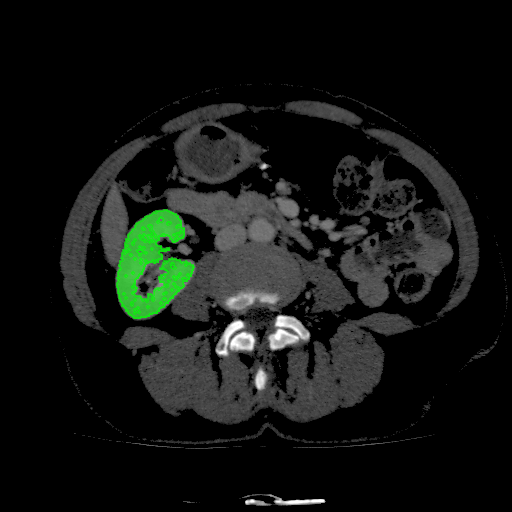

For MSER tracking, Donoser and Bischof [5] presented three different applications; license plate tracking, face tracking and the segmentation of a fiber network. In the third application, a fiber network is reconstructed in 3D by tracking a slice of the data along the axis orthogonal to the image data. Analogously, we track organs in slices of a Computed Tomography (CT) scan, to generate a 3D segmentation. We use the CT data provided in the 3DIRCADb dataset222The dataset is available on http://ircad.fr/research/3d-ircadb-01 [14].

To initialize the tracking process, the organ is segmented in an arbitrary slice of the CT data by a bounding box. The most stable MSHR is then selected in the initialization process for tracking. The respective MSHR is tracked through the slice data along the axis orthogonal to the image data. An example of the tracked regions is visualized for two examples in Fig. 7. Given the segmentations of the single slices, the organ can be reconstructed in 3D. We compare the reconstruction for MSER and MSHR tracking in Fig. 8. To enhance the visualization, the datapoints are triangulated and the surface normals calculated. Since the contrast of the organs can be very low in CT images, the MSER tracking has difficulties catching the organ boundaries. Furthermore, the organ is sometimes partely lighter and darker than the background, which may lead to MSER tracking failure. The proposed MSHR tracking copes well with these difficulties, and the reconstructions are significantly better.

Figure 7: Two examples sequences from the 3DIRCADb dataset [14]. Given an initial selection of a single slice (the middle image in (a) and (b)) of the organ, the proposed MSHR tracking tracks the region forward and backwards in space. The segmented slices can be used to reconstruct the organ, see Fig. 8 for an example reconstruction.